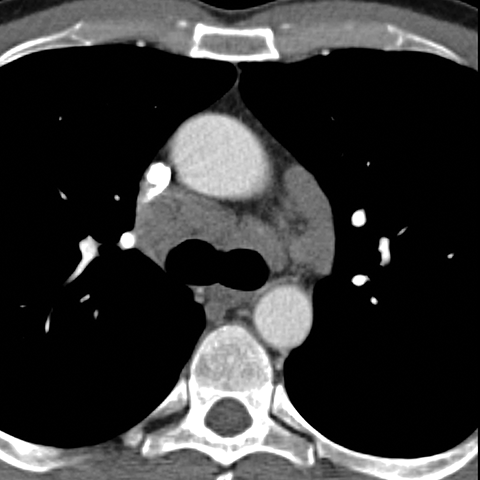

Mediastinal Lymph Nodes in NHL (Axial CT) [3 of 4]